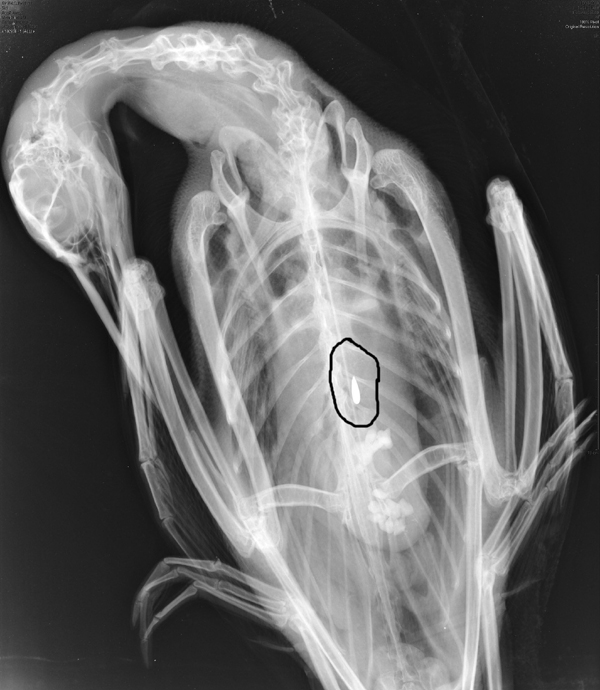

Bill aims to get lead out of Maine loons

It would ban fishermen from using sinkers and jigs made of lead, but some say the move is unnecessary.

Legislation would protect loons by banning lead sinkers

The former head of the Sportsman’s Alliance of Maine told lawmakers Thursday that fishermen shouldn’t continue using lead sinkers and jigs that harm loons on local lakes.